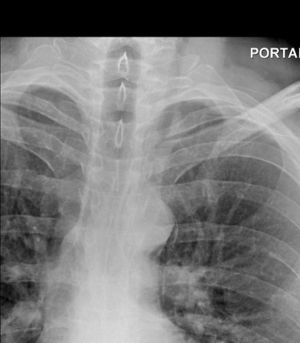

- CXR: 90% will have radiographic abnormalities, nonspecific in nature

- Pneumomediastinum

- Abnormal cardiomediastinal contour

- Pneumothorax

- Pleural effusion